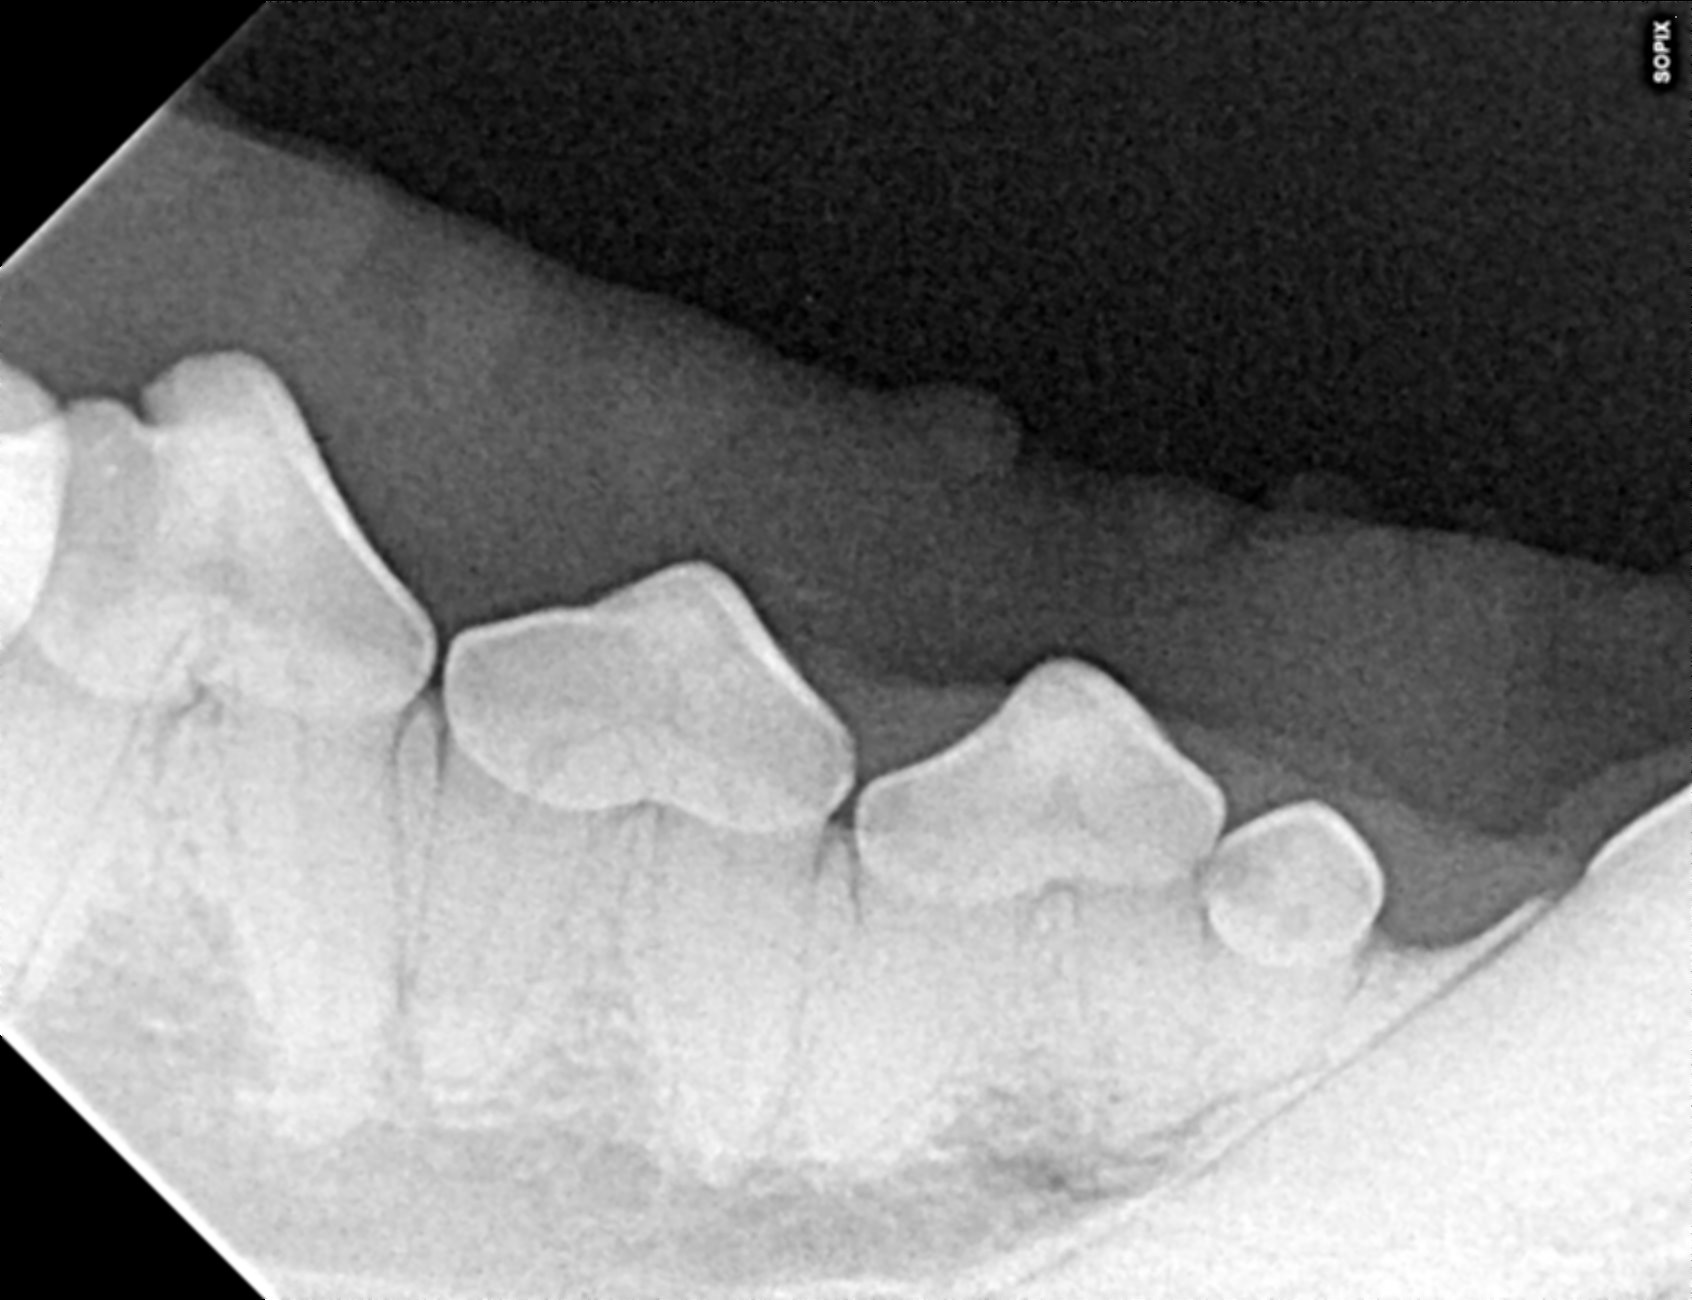

The prophylactic dental includes x-rays of all the teeth, ultrasonic scaling of the plaque and tartar from the teeth, polishing, and fluoride treatment. It is impossible to determine the full extent of dentistry your pet needs until they are under anesthesia and we can examine each tooth individually, but we can give an estimate of your pets dental status and needs during your routine exam.